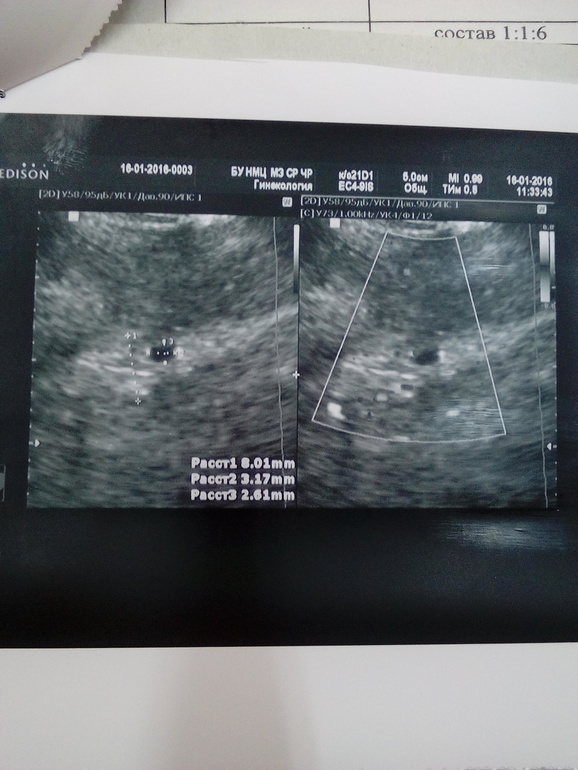

Не виден полип на узи

Не виден полип на узи 115 фото